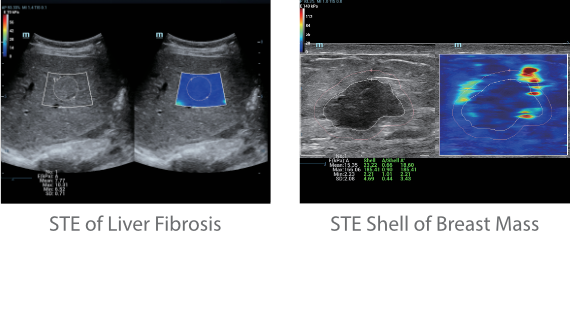

Since the company was founded, Mindray has been continuously exploring new ways to improve diagnostic confidence. Powered by the most revolutionary ZONE Sonography? Technology, Resona 7ŌĆÖs new ZST+ platform brings ultrasound image quality to a higher level by zone acquisition and channel data processing.

As well as the premium level image quality, Resona 7 also enhances clinical research capabilities with the revolutionary V Flow for vascular hemodynamic evaluation, and the most intelligent plane acquisition from 3D datasets for fetal CNS diagnosis. Combining the most intuitive gesture-based multi-touch operation and all the essential clinical features, Resona 7 is truly leading new waves in ultrasound innovation.